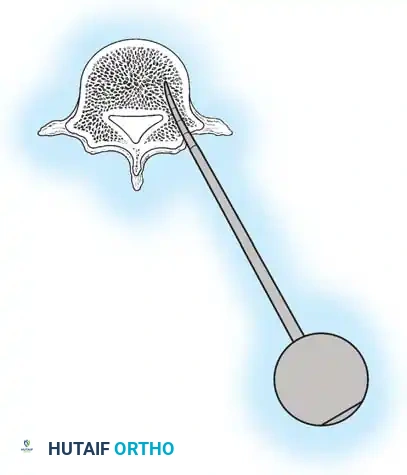

The Moe Technique (Lumbar Spine)

In the lumbar spine, the facet joints are oriented in a more sagittal plane, necessitating a modified approach.

Fig. 38-27: The Moe technique adapted for lumbar facet fusion, addressing the sagittal orientation of the joints.

- Utilize a small osteotome or a needle-nose rongeur to resect the adjoining joint surfaces.

- This creates a distinct rectangular defect within the sagittally oriented joint space.

- Pack this defect forcefully with cancellous bone graft.

- Proceed to decorticate the entire exposed posterior elements (laminae and transverse processes) using Cobb gouges, always directing force away from the spinal canal.